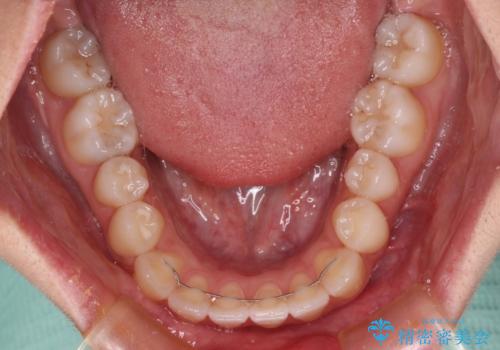

- 前歯のクロスバイトが気になり、インビザラインによる矯正治療を希望して来院された患者様です。

上顎側切歯(上の真ん中から2番目の歯)が舌側転位している場合、インビザラインでは仕上げきれないことが多く、更には無理して動かそうとすると歯髄壊死を起こすリスクが高いと言われています。

インビザラインで歯列を移動する前に、上顎前歯をワイヤー矯正で整え、その後上下歯列をインビザラインにて矯正治療を行うこととしました。

舌側転位している側切歯特有の、切縁の位置が不揃いであったり、根元が内側に引っ込んだ状態であったりという、インビザライン独特の仕上がりになることなく、きれいに整った歯列とすることができました。